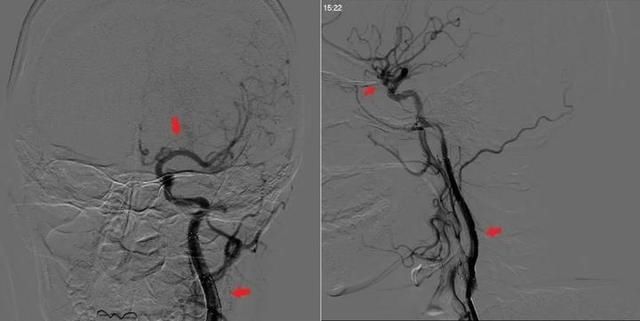

文章图片

取栓手术后(右图),颅内血管被打通后重新显影,颈动脉夹层被支架修复。